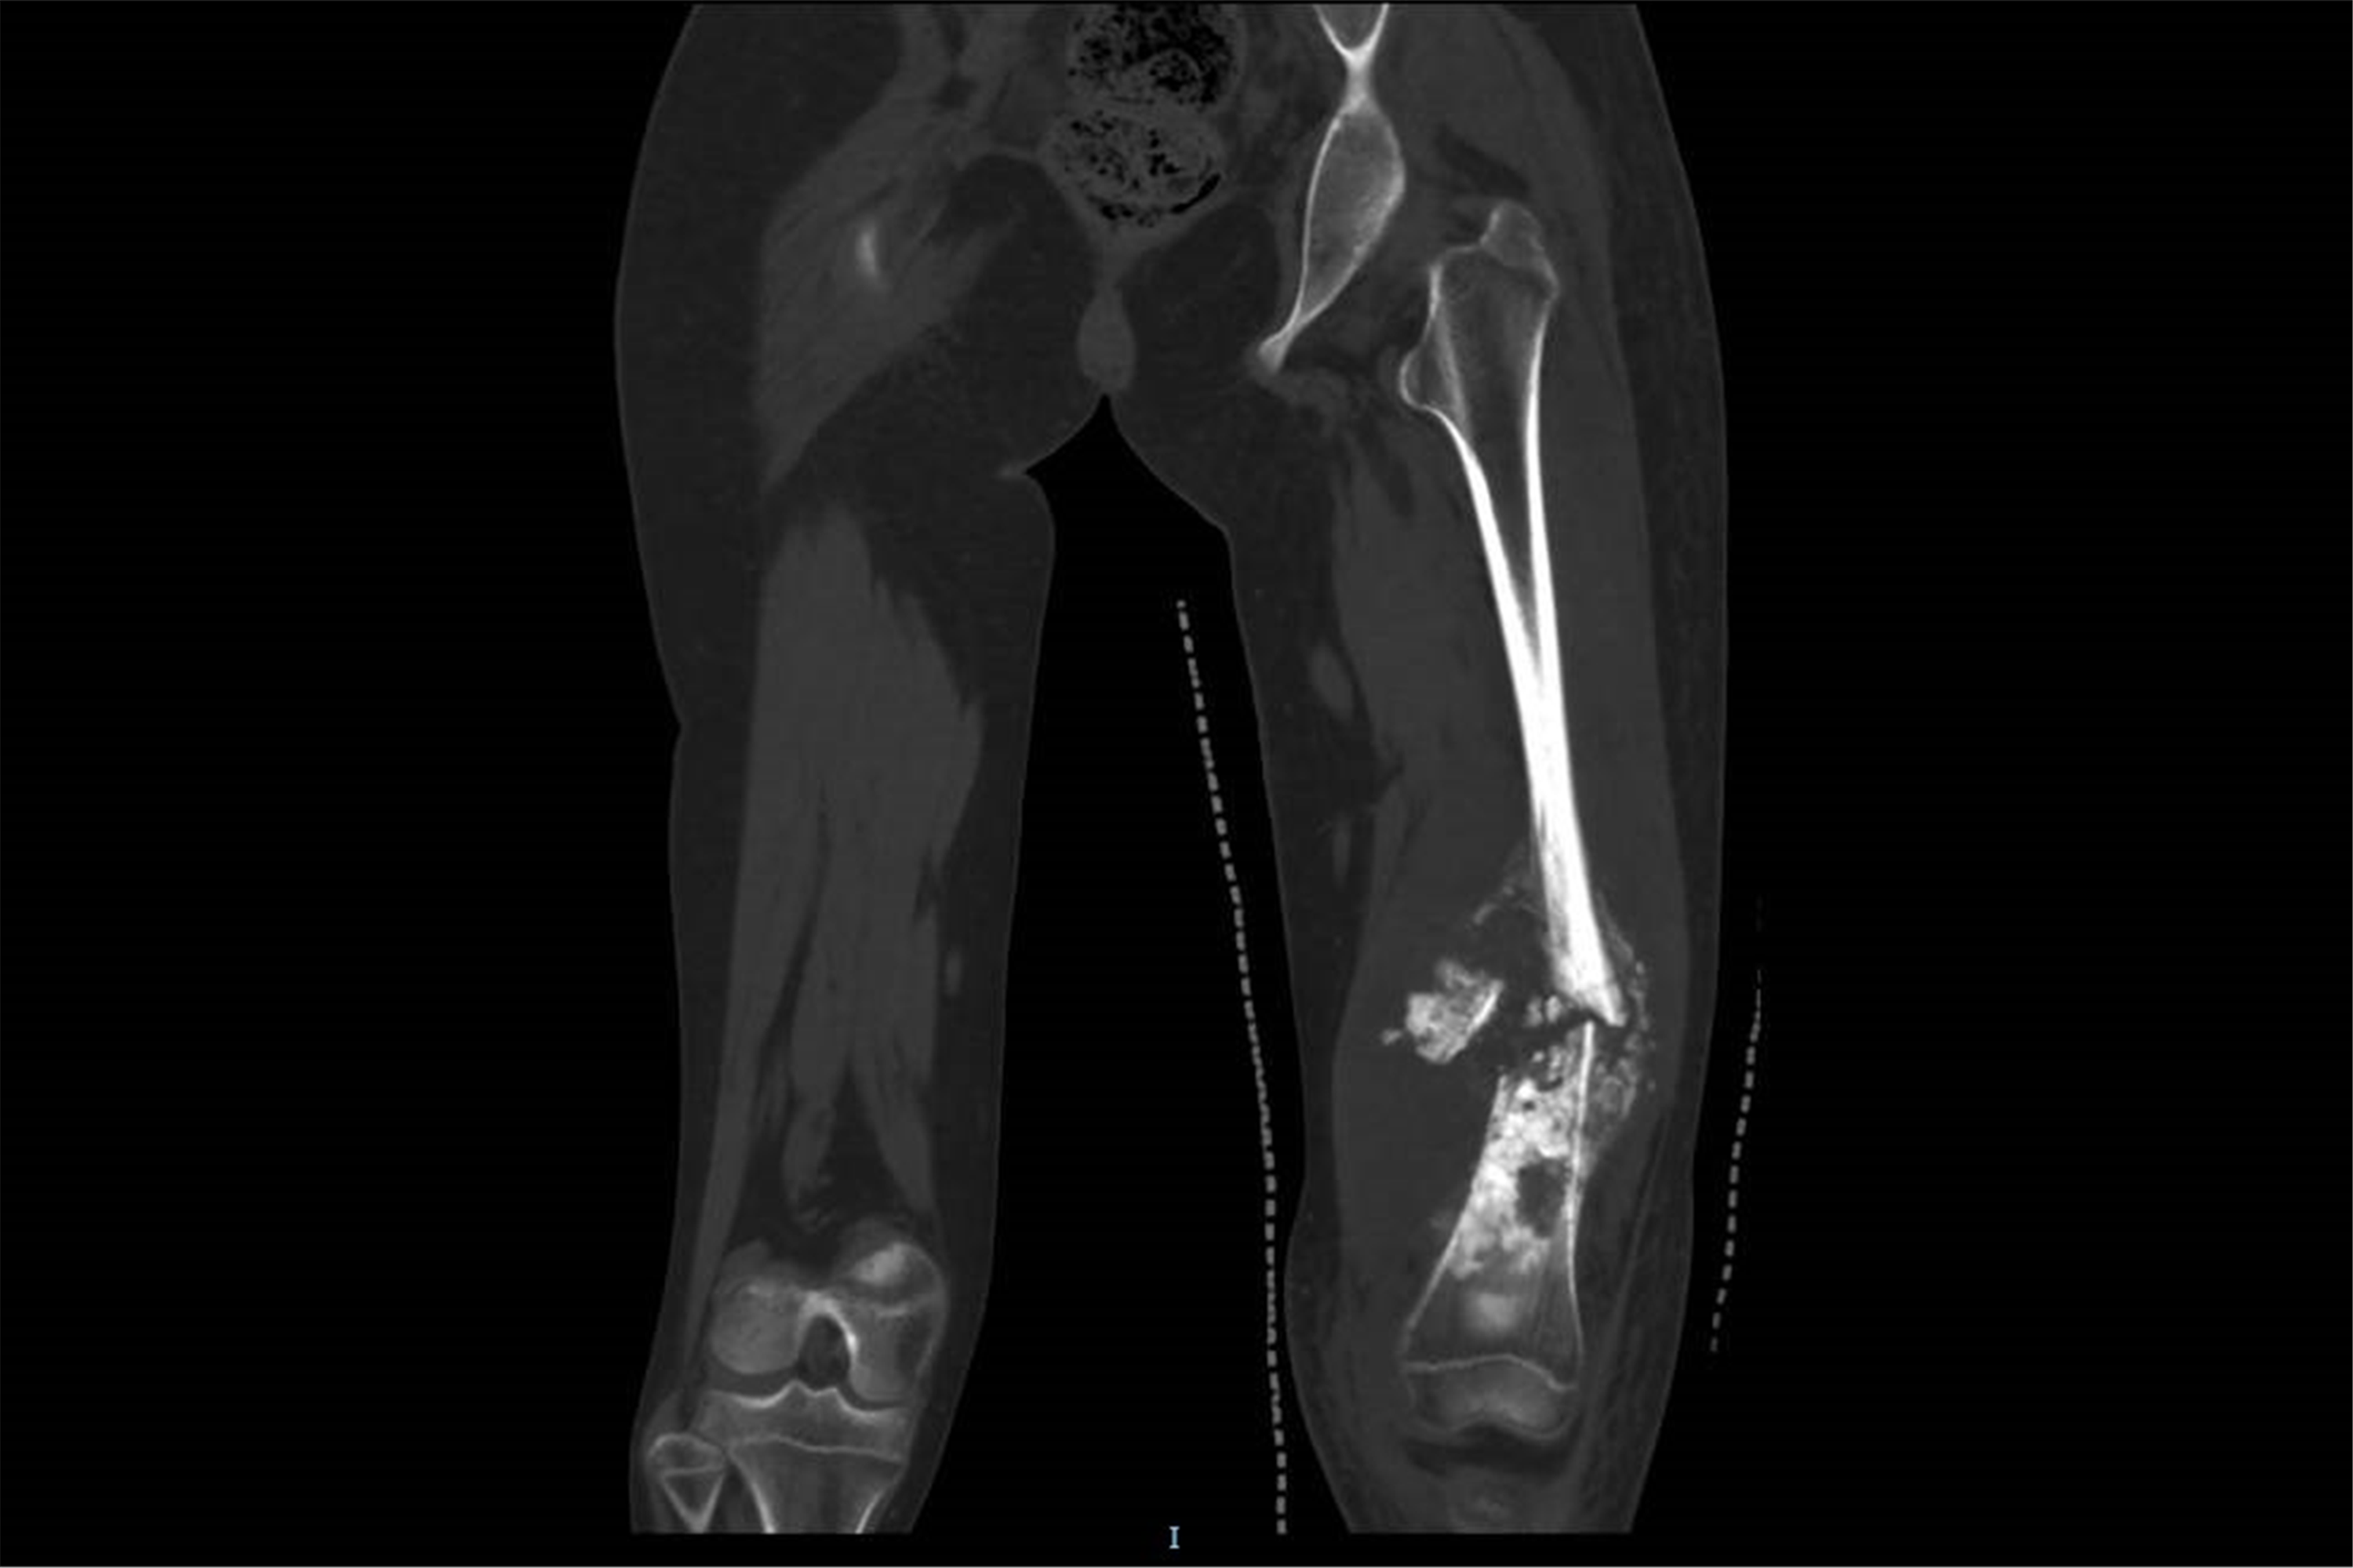

这是小鱼的术前CT影像。

针对小鱼的病情——股骨下段肿瘤长达15厘米、宽度达6.5厘米,王克及其团队制定了“新辅助化疗+保肢手术”的个体化方案。经过4个月8次高强度化疗,患儿肿瘤宽度从6.5厘米缩小至3.5厘米,腿围由38厘米降至33厘米,为后续保肢手术创造了关键条件。